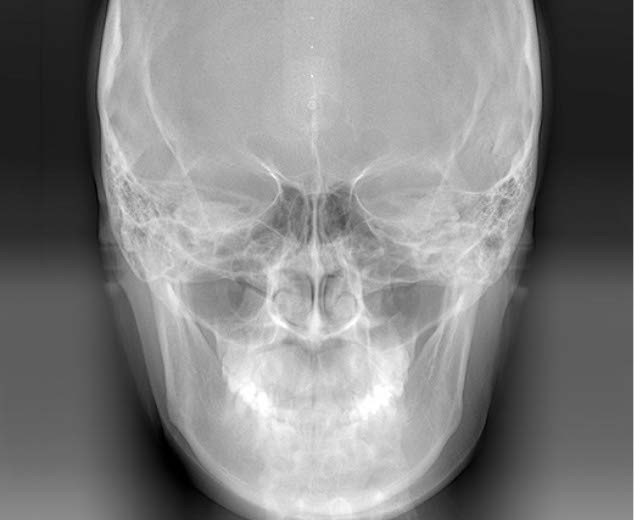

初診相談後、治療をご希望される場合は、初診検査を実施します。この検査で、患者様の現在の口腔内の状態を確認します。

顔貌・口腔内写真の撮影

レントゲン撮影

歯型の模型採取